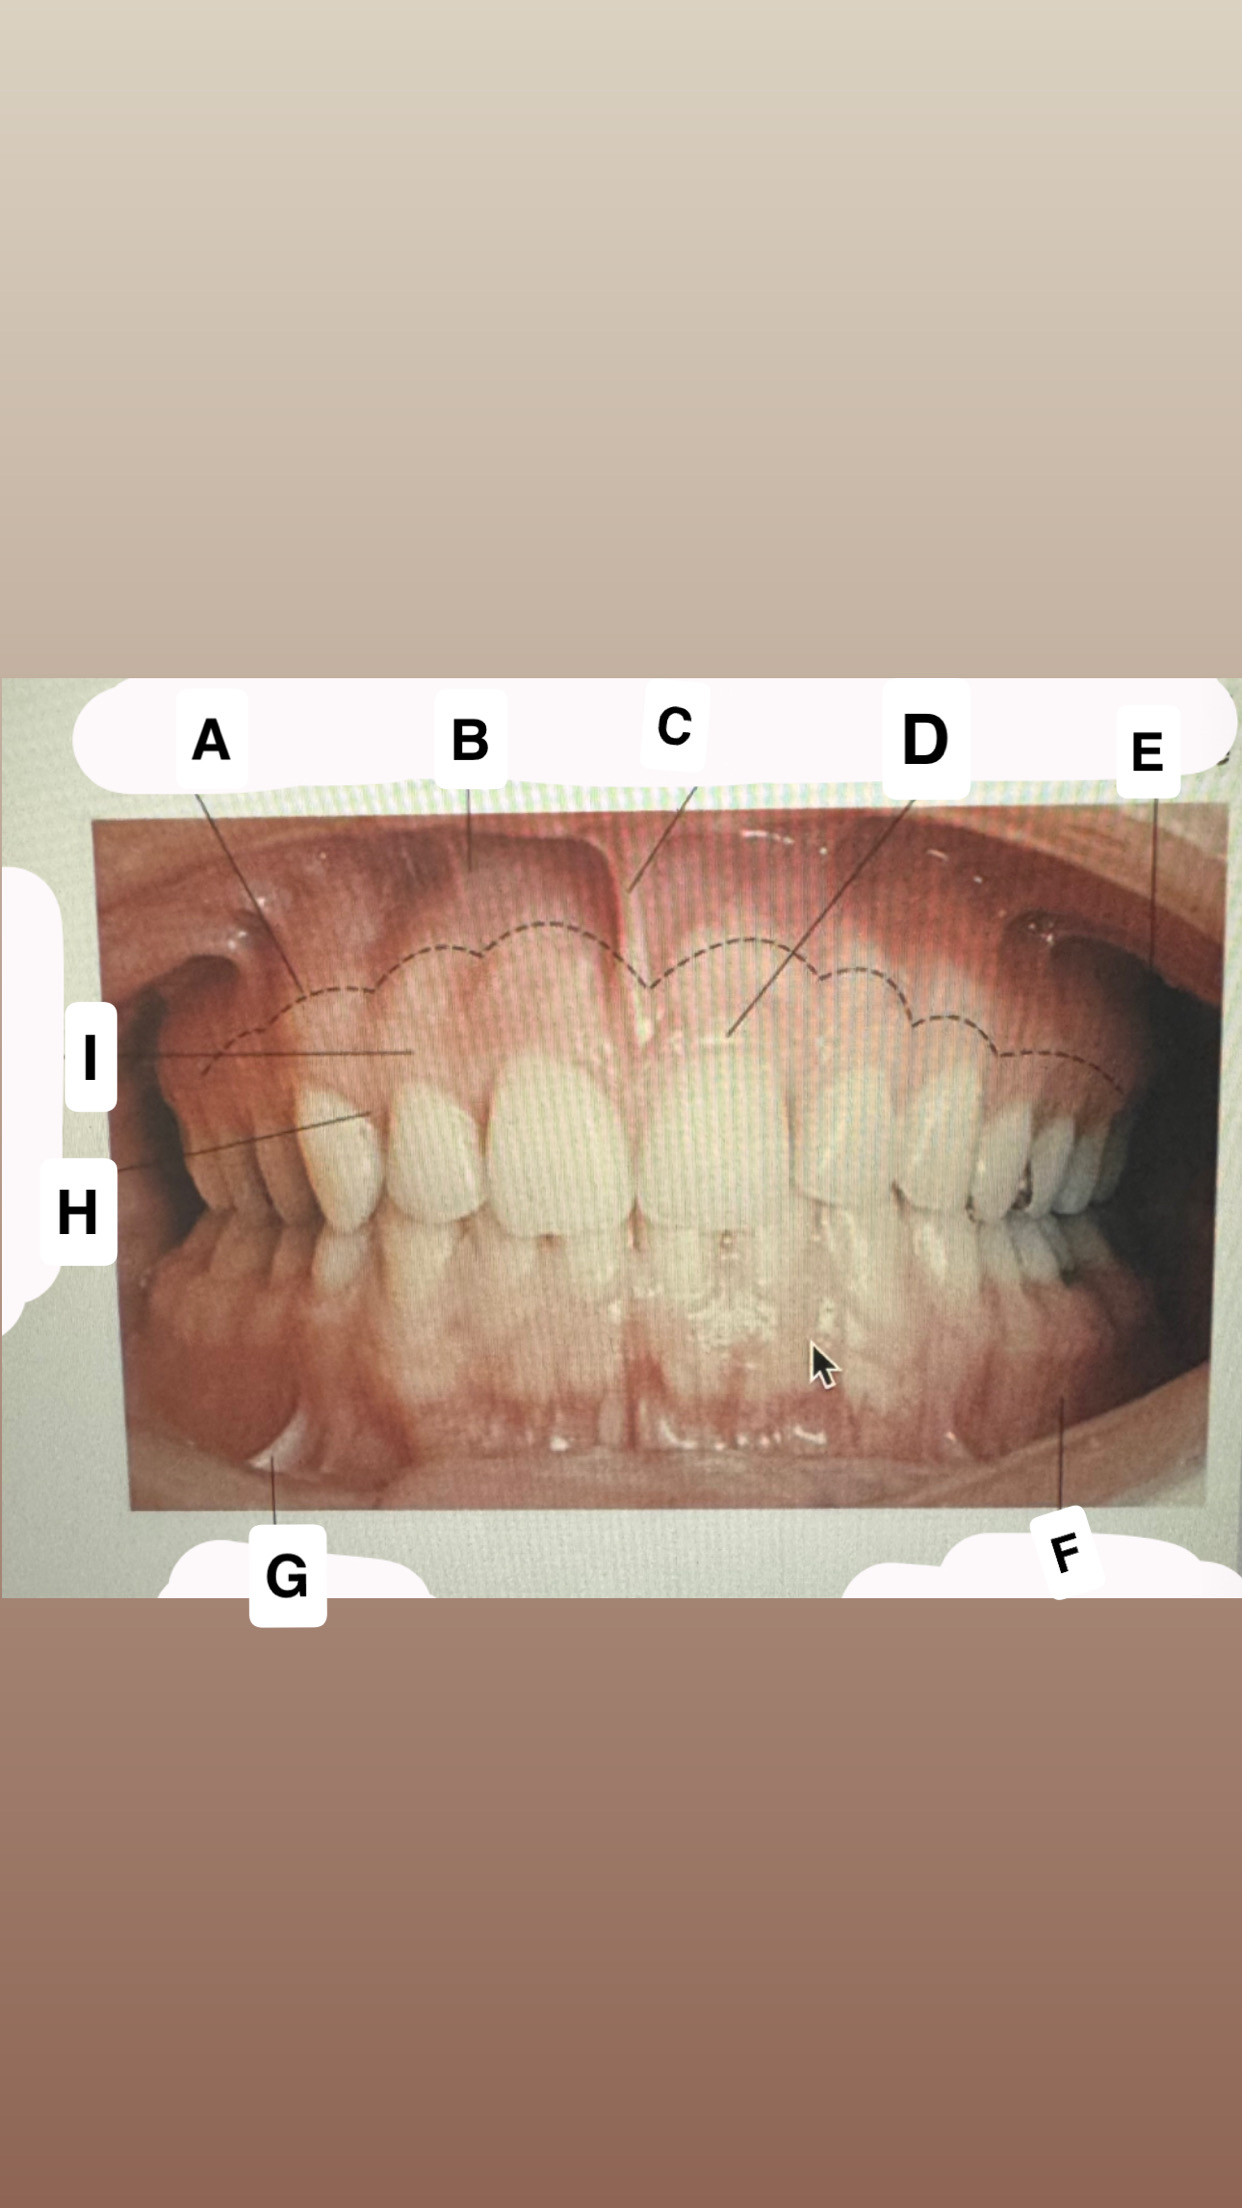

<p>Identify A</p>

Mucogingival

junction

<p>Identify B</p>

Alveolar

mucose

<p>Identify C</p>

Maxillary labial frenum

<p>Identify D</p>

Marginal gingiva

<p>Identify E</p>

Maxillary vestibule

<p>Identify F</p>

Mandibular vestibule

<p>Identify G</p>

Mandibular buccal frenum

<p>Identify H</p>

Interdental-gingiva

<p>Identify I</p>

Attached gingiva